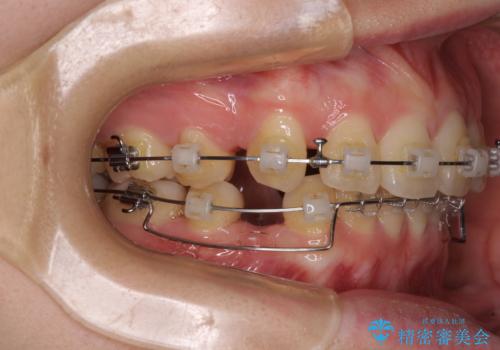

- クリアブラケット

前突間を改善するため、上顎左右の第一小臼歯を抜歯してワイヤー装置にて矯正治療を行うこととしました。

深い咬み合わせは上顎前歯を引っ込ませる大きな障害となるため、咬み合わせの改善が非常に重要となります。やや期間はかかりましたが、当初狙った通りの仕上がりで治療を終えることができました。